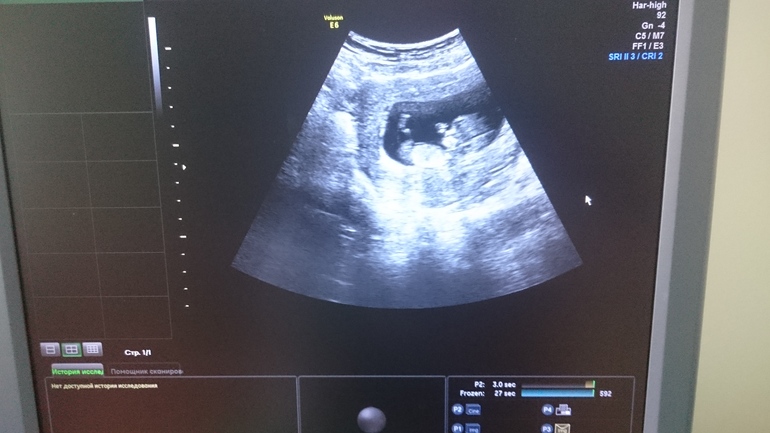

Девочка vs мальчик. Фото со скрининга

Всем здравствуйте, на прошлой неделе я делала первый скрининг, про пол ничего не сказали, но разрешили сфоткать экран. Может тут есть кто-то кто разбирается? ЧСС у нас 160 ударов в минуту.